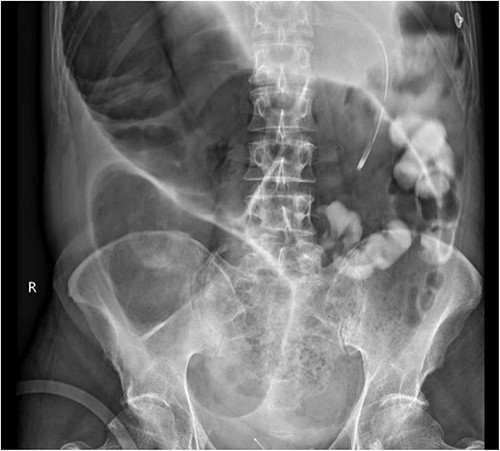

A subsequent gastrograffin study was performed the next day with persistent contrast in nondilated small bowel at 8 hours and nil therapeutic clinical improvement (Fig. 3).

Gastrograffin study demonstrating markedly dilated gas filled loop of large bowel seen extending from the pelvis into the right upper quadrant, consistent with a dilated loop of redundant sigmoid, with no obvious contrast in the colon but some contrast in the small bowel loops in the left upper quadrant.